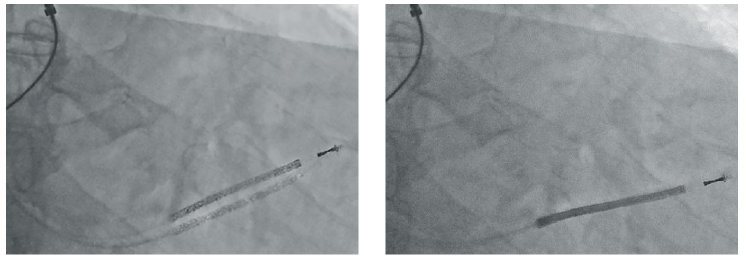

With advanced contrast optimization, Quantum-Stream excels in demanding applications: from cardiovascular imaging, where subtle vessel details must remain visible, to spine procedures with strong density variations, where contrast stabilization prevents loss of information. Supported by a unique, compact and powerful 30 kW generator, the system achieves these performance gains without increase in patient dose – combining precision with patient safety.

ZAIP features advanced real-time algorithms designed to deliver optimal fluoroscopic image quality. A spatial, edge-preserving noise reduction filter suppresses background noise while maintaining fine anatomical detail. In parallel, an intelligent motion-sensitive temporal filter adapts to patient or instrument movement, reducing noise effectively without introducing blur.

Complementing these noise controls, frequency-based contrast stabilization selectively enhances clinically relevant structures while preventing oversaturation in areas of varying density.

Together, these technologies ensure consistently clear and detailed visualization – from guidewires and catheters to complex anatomical regions – even under low-dose conditions.